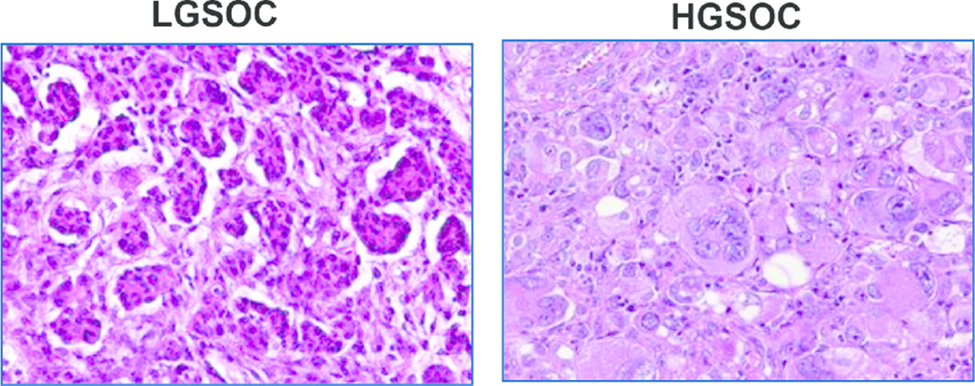

ჰისტომოფოლოგია

LGSOC ჰისტოლოგურად წარმოდგენილია მონოტონური, კუბური მცირედ ეოზინოფილური უჯრედების სახით, ატიპია მერყეობს მუბუქიდან-საშუალომდე,ხოლო მიტოზების რაოდენობა არ აღემატება 12 მიტოზს 10 HPF(მაღალი გამადიდებელი) ველის ფარგლებში – რაც დაბალი პროლიფერაციული აქტივობის მაჩვენებელია.